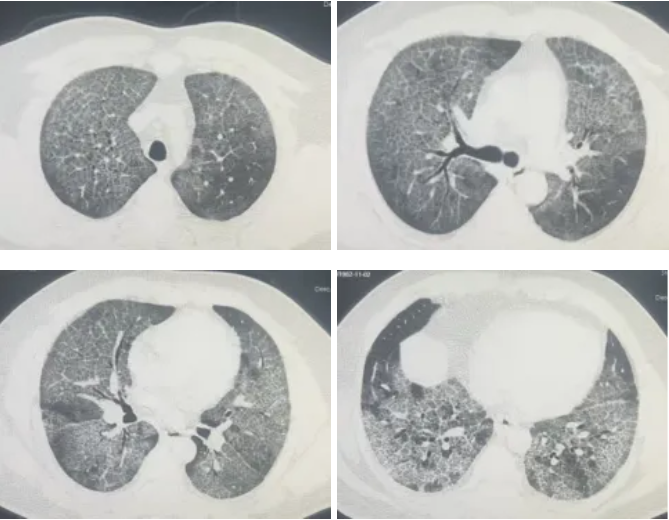

接诊后,呼吸与危重症医学科冯永海团队对孟师傅的胸部CT进行了细致分析,发现双肺弥漫性改变,高度怀疑肺泡蛋白沉积症。

▲ 灌洗前胸部CT